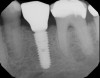

A 4.8 mm x 10 mm implant (Straumann® Bone Level Tapered [BLT], Straumann) had been placed at the mandibular first molar site and was ready for restoration. A custom healing abutment was fabricated and inserted at the time of surgical implant placement and soft tissue was sutured around the abutment using 4/0 Glycolon sutures (Osteogenics Biomedical, osteogenics.com) (Figure 13). A periapical x-ray was taken at the time of placement of the custom healing abutment to confirm full seating (Figure 14).

Fig 14. A periapical radiograph of the custom healing abutment on the implant demonstrated the development of a natural emergence profile for a mandibular molar to replicate the missing natural tooth.